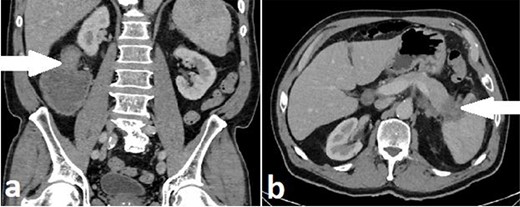

A 71-year-old man with a background of cardiac disease and obstructive sleep apnoea presented to the emergency department with symptoms of large bowel obstruction. Urgent CT abdomen and pelvis revealed short segment hepatic flexure thickening and stranding with evidence of obstruction at this point. An additional soft tissue mass in the tail of the pancreas encasing the splenic vasculature was reported as suspicious for metastatic disease from a primary colonic malignancy or a synchronous primary pancreatic malignancy (Fig. 4). Serum CEA was 5.32ug/L and serum Ca 19-9 was significantly elevated at 1180u/ml.

Case B. Portal venous phase CT scan of the abdomen. Coronal view of short segment hepatic flexure thickening (arrow) with proximal large bowel obstruction (a) and axial view of soft tissue mass (arrow) at tail of pancreas (b).